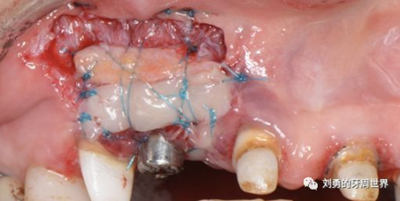

該方式齦瓣固定的效果差,術(shù)后血供差,為了改善血供,我們提倡下面的改良縫合方式,血供更好,成功率更高,如下圖:

通過用縫線壓迫的方式固定,術(shù)后愈合的過程齦瓣始終與受區(qū)骨膜貼合,而不會(huì)移動(dòng)。

但是該方法對(duì)于縫合技術(shù)要求較高,因此本人嘗試了新的方法,膜釘固定:

該方法操作簡(jiǎn)單,但是需要擇期局麻下拆除膜釘。